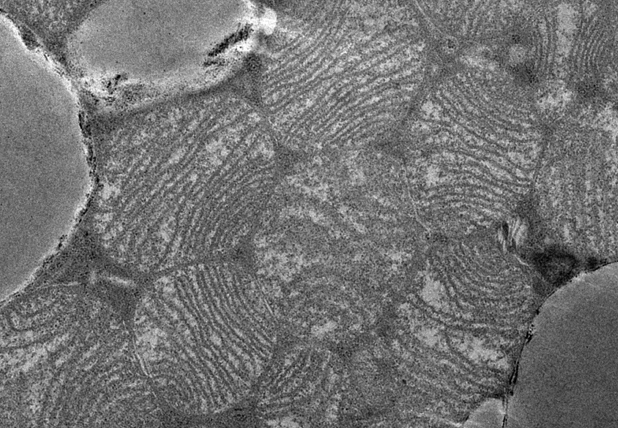

In humans and mammals, a general distinction is made between at least two different types of fat depots, white and brown fat tissue. The former is much more common in the human body, stores fat, and is preferably located in the commonly known pads on the abdomen, buttocks and thighs. In case of increased energy demand, the body can fall back on these depots. Brown fat, on the other hand, burns energy while releasing heat, which is why babies have a lot of it. However, the number of these cells decreases steadily after the newborn age and in cases of obesity.

"Brown adipose tissue has been identified as a way of helping with weight loss because it can burn large amounts of calories," explains Elena Schmidt, a PhD student in Jan-Wilhelm Kornfeld's research group in Cologne. 40-50 g of brown fat cells alone could burn 20% more calories. Therefore, an activation of the brown fat cells is a new way to lose weight.